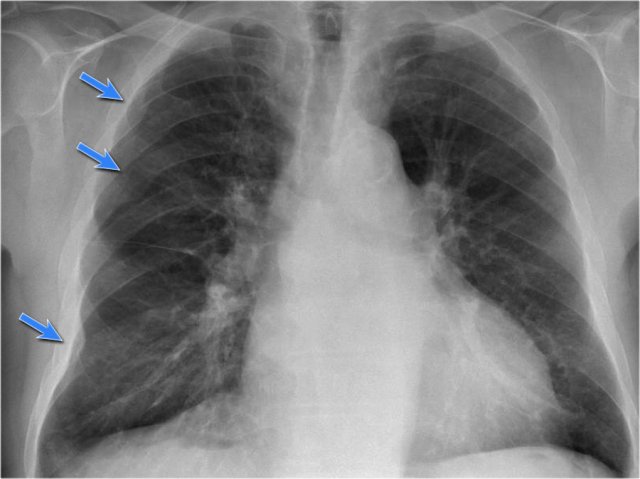

The CXR shows multiple opacities.

They have irregular shapes and do not look like a lung masses or consolidations.

Some of these opacities are clearly bordering the chest wall (red arrows).

All these findings indicate that we are dealing asbestos related pleural plaques.

Asbestos related pleural plaques are usually:

- bilateral and extensive.